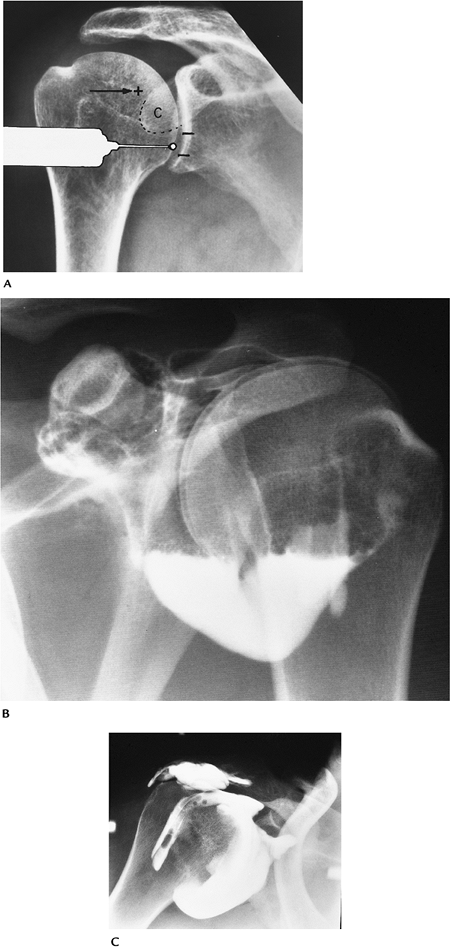

FIGURE 7-18 Arthrography. (A) Usual anterior entry site for shoulder arthrography and the rotator cuff interval entry site (+). (B) Normal double-contrast arthrogram with no air or contrast in the subacromial bursa. (C) Single-contrast arthrogram with contrast in the tear and subacromial bursa.